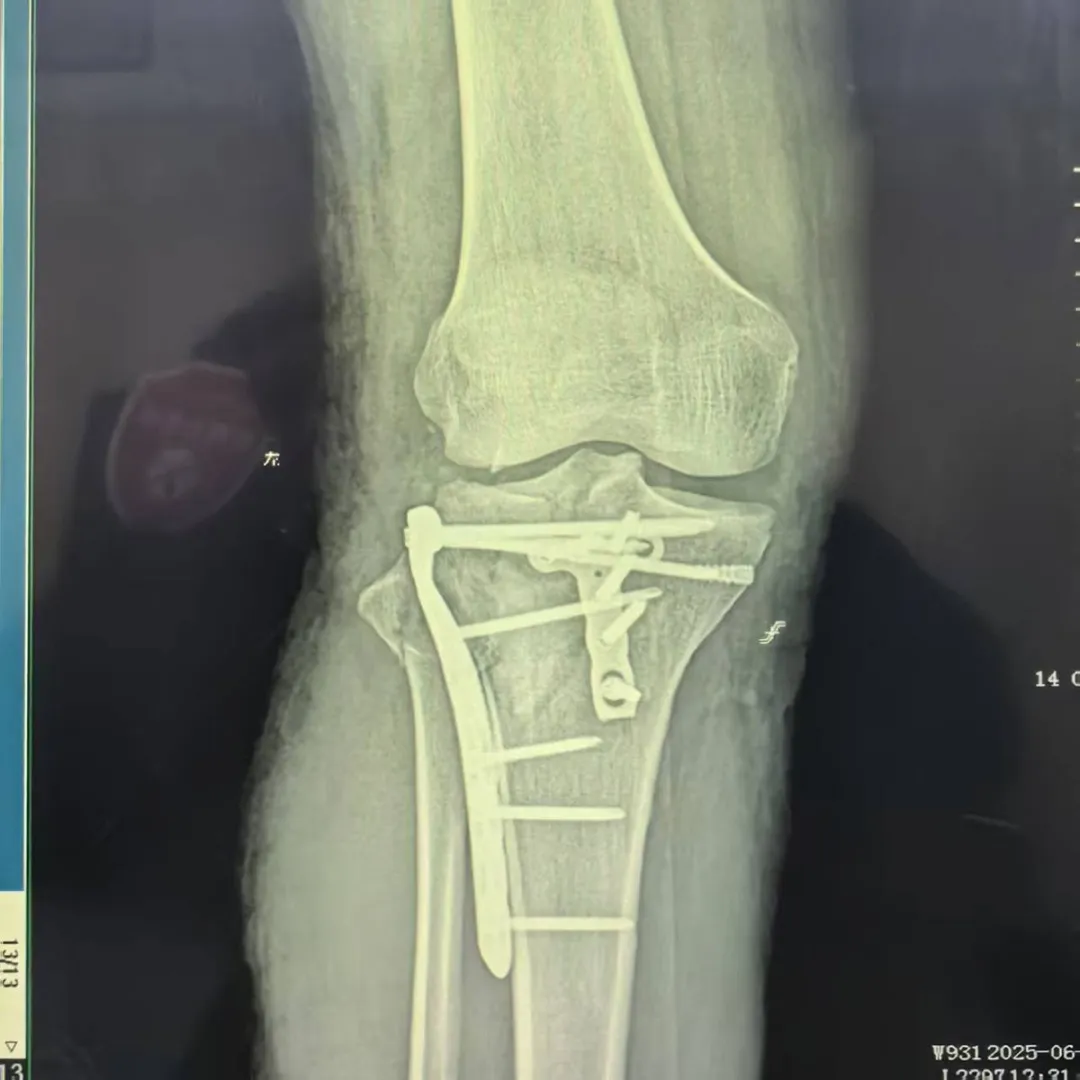

病例难点:直面手术挑战

患者石女士,34岁,因高处坠落导致右膝严重损伤。经过详细的影像学检查,诊断确认:胫骨平台后外侧粉碎性骨折(Schatzker Ⅱ型)、膝关节前、后交叉韧带及内外侧副韧带损伤、外侧半月板后角Ⅲ度损伤,内侧半月板后角Ⅰ度损伤。

技术创新:精准手术解决方案

面对这一复杂病例,科室医疗团队组织全科进行术前讨论,结合最新版《胫骨平台骨折诊断与治疗专家共识》,经过精密规划,最终决定采用改良Frosch后外侧入路这一先进术式。

个性化选择后外侧支撑钢板

实现骨折块的稳定固定